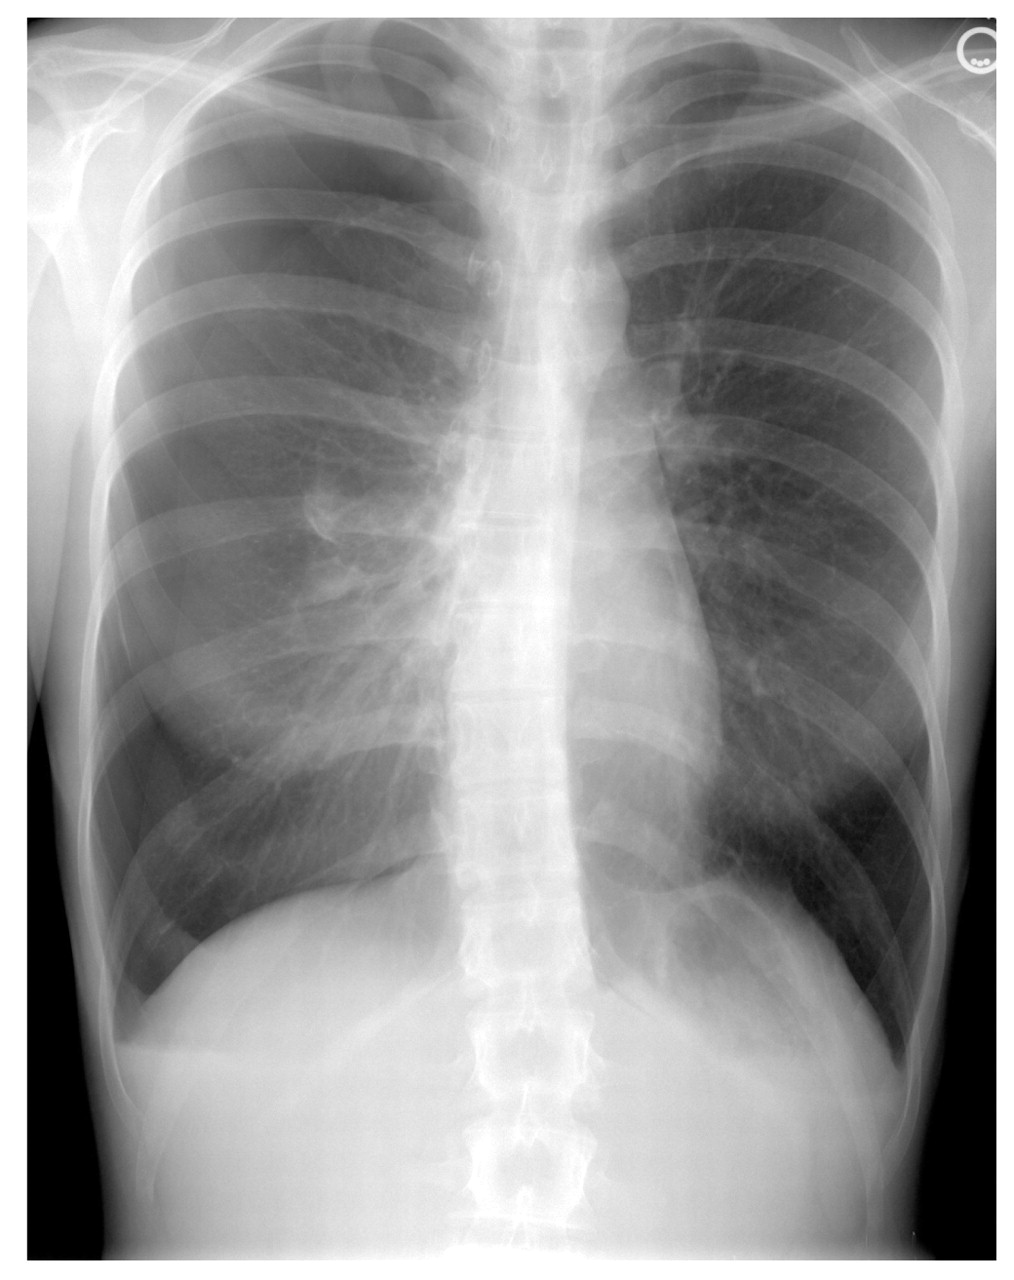

Physical examination revealed a healthy but slender white woman in no obvious distress. Although the patient had symmetric rise and fall of the chest with respiration, she had decreased breath sounds to auscultation and hyperresonance to percussion over the right lung fields. There was no evidence of ecchymosis, edema, or erythema of the thorax. Tactile fremitus, egophony, and bronchophony were not assessed. Tenderness to palpation was present at ribs 4 through 7 on the patient's right side. The remainder of her physical examination was unremarkable. A chest radiograph revealed a pneumothorax greater than 50% on the right side. There were neither bony fractures nor evidence of tension pneumothorax (Figure 1).

Diagnostic chest radiograph of a 20-year-old woman who received a “bear hug” manual home remedy and was seen by physicians at Carl R. Darnall Army Medical Center (Fort Hood, Tex). This radiographic image reveals a pneumothorax greater than 50% on the right side with no bony fractures or evidence of tension pneumothorax.